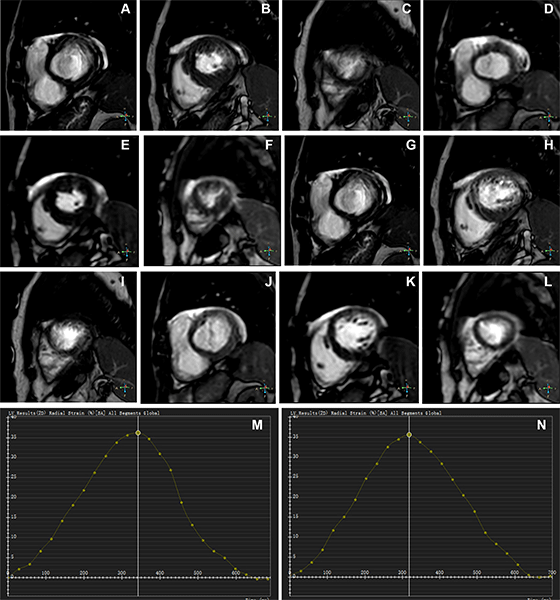

Representative MR images of participants with difficulty with breath holding and arrhythmia. Zhang et al RYCTI 250298

Representative images of participants with difficulty with breath holding and arrhythmia. In the lower right corner of A–L, the position coordinates of the images are marked. Short-axis (SA) view images in the end-systole (A–F) and end-diastole (G–L) phases in participants with atrial fibrillation. (A–C, G–I) Balanced steady-state free precession (bSSFP) cardiac cine. (D–F, J–L) Deep learning–enhanced compressed sensing (AI-CS) single-shot cardiac cine. In contrast to AI-CS single-shot cardiac cine, endocardial contours were challenging to identify on conventional segmented cine in midventricular and apical sections. (M) Line graph of time curve during the whole cardiac cycle obtained from bSSFP cardiac cine. (N) Line graph of time curve during the whole cardiac cycle obtained from AI-CS single-shot cardiac cine. LV = left ventricle., 2D = two-dimensional.